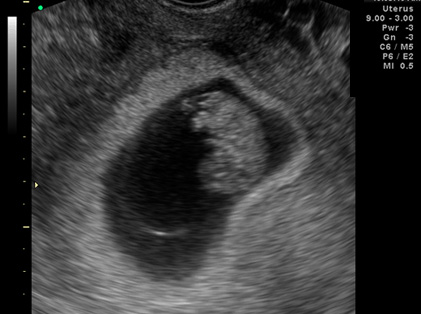

임신 후기 초음파 영상(출처 : 대한초음파의학회)

시기에 따라 초음파를 통해 확인하는 항목이 달라요! 임신 초기에는 질 내 초음파로 자궁 안 태낭 (태아가 들어있는 주머니) 또는 태아 심박 여부를 확인했었죠? 임신 8-10주에는 CRL (태아의 머리부터 엉덩이까지 길이) 측정을 통해 임신 주수를 확정해요. 이시기의 아이는 CRL에 개인차가 없거든요! 장신의 농구선수도, 귀여운 체조선수도 CRL 수치는 비슷비슷! 성별을 알려주는 것도 이 초음파예요!

태아 기형을 진단하며 기형아 검사와 병행해 염색체 이상 진단 등 선천성 기형을 찾아낼 수 있어요. 무뇌아나 심한 태아 수종 등의 기형 확인도 가능해요. 임신 후기에는 태아의 외형 및 주요 내부 장기의 이상이나 기형 진단을 위해 정밀 초음파 검사를 해요. 또 태아의 외형적 모습을 세밀하게 진단하기 위해 입체초음파 검사 (3D입체초음파)를 하기도 해요. 무조건 3D 입체초음파가 더 고급 기술같아! 라고 생각하는 것은 틀려요! 2D 초음파는 신체 단면이 영상을 비추므로 내장 등 몸 내부 모습을 보는데 매우 효과적이예요.